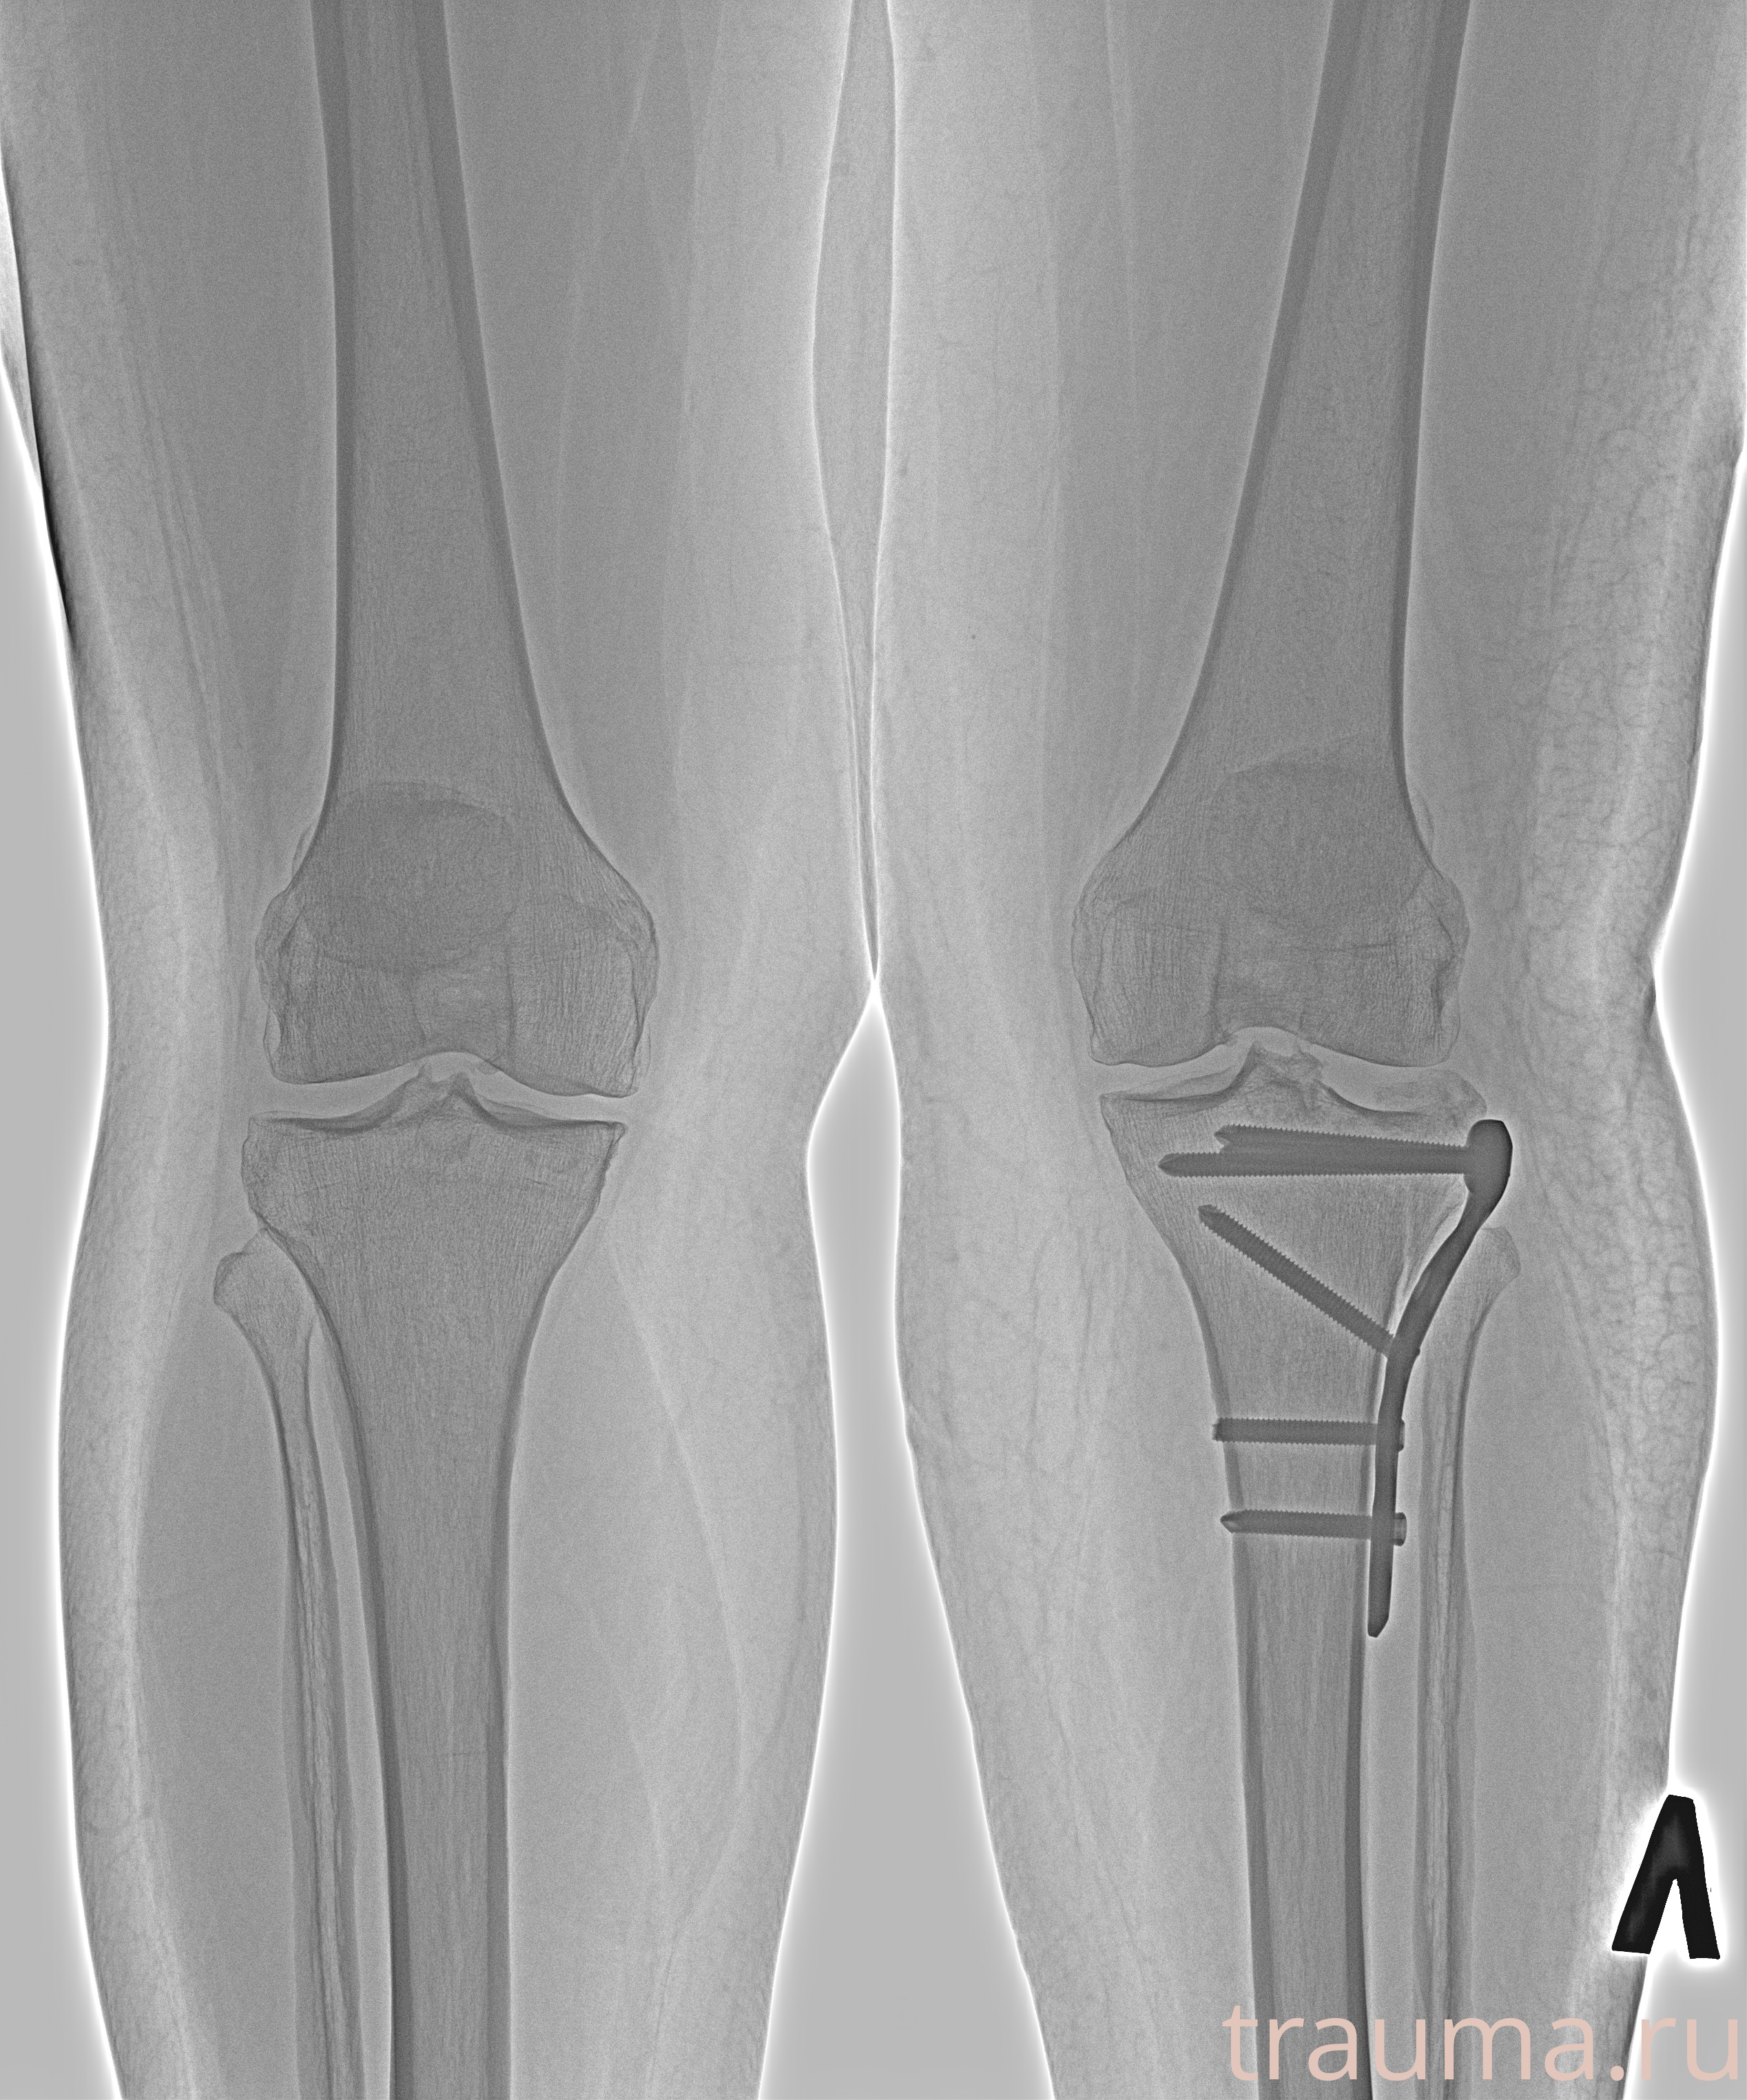

Рентгенограммы

Рентген на дому: по вашему адресу приезжает врач-рентгенолог, травматолог-ортопед с мобильным рентгеновским аппаратом, проводит диагностику травмы или заболевания, делает необходимые рентгенограммы, дает рекомендации по дальнейшему лечению. Получить качественные снимки в домашних условиях возможно благодаря уникальной методике, разработанной МосРентген Центром для института  Склифосовского